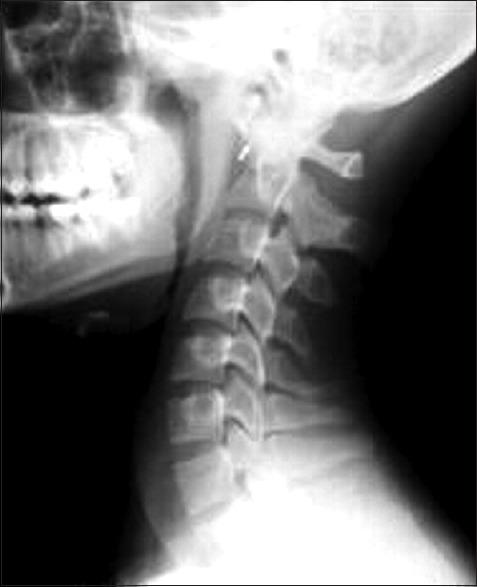

Grisel's syndrome is a nontraumatic subluxation of atlanto-axial joint which is associated with inflammatory conditions of head and neck and occurs primarily in children. Anesthetic management is such cases constitute a multitude of challenges, especially related to the airway management. We presented here a case of 16-year-old male child weighing 23 kg, came to our hospital for the treatment of torticollis who was previously treated with intravenous antibiotics for rhinopharyngitis and diagnosed as a case of Grisel's syndrome. The child was operated on for unilateral resection of sternocleidomastoid muscle under general anesthesia. This case report pertains to the successful airway and anesthetic management in the background of difficult airway.

格里塞尔综合征是一种寰枢关节非创伤性半脱位,与头颈部炎症性疾病相关,主要发生于儿童。此类病例的麻醉管理面临诸多挑战,尤其是气道管理方面。我们在此报告一例16岁男性患儿,体重23千克,因斜颈来我院治疗,该患儿此前因鼻咽炎接受静脉抗生素治疗,被诊断为格里塞尔综合征。患儿在全身麻醉下行胸锁乳突肌单侧切除术。本病例报告涉及在困难气道背景下成功的气道和麻醉管理。